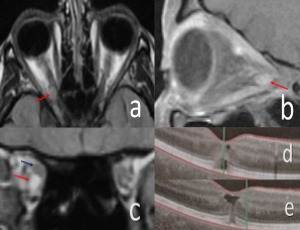

A case of trigeminal neuralgia after COVID-19

The trigeminal nerve is one of twelve pairs of cranial nerves that attach to the brain. The name “trigeminal” literally means three twins and refers to the fact that the fifth cranial nerve has three major divisions: the ophthalmic (V1), the maxillary (V2), and the mandibular (V3) [1]. The trigeminal nerve is the major sensory nerve of the face and is the nerve of the first branchial arch.